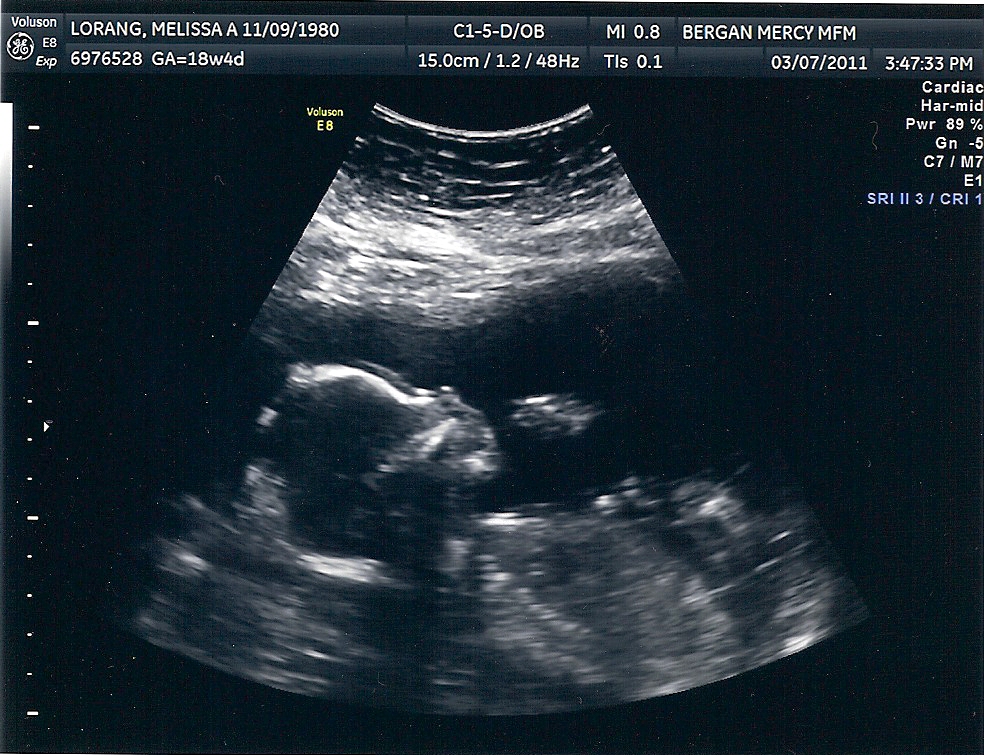

So without further adieu,

I am pleased to share with you

a picture of our dear son Sam.